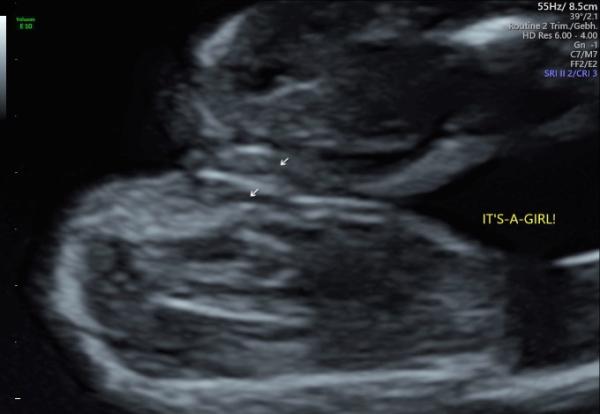

Ich hab hier ein Bild von meiner ersten Tochter. Aber ich finde auch, dass es bei dir eindeutig ein Mädchen ist.

Bild zu